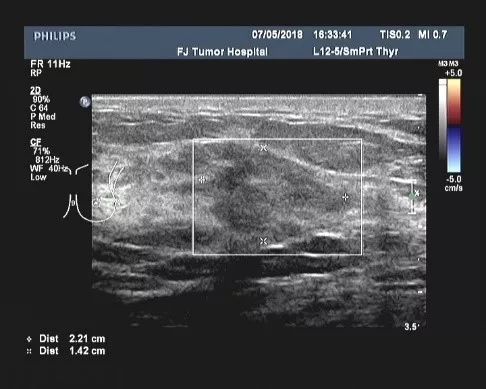

2018-05-25、2018-06-14改为nab-PHL方案(白蛋白结合型紫杉醇400mg+曲妥珠单抗408mg+拉帕替尼1000mg )化疗2周期。

▎疗效评估:B超(2018-07):左乳2-3点处探及一低回声区,大小约2.2cm×1.4cm,边缘不规则,可见成角、毛刺,内部回声不均;左腋中、下组探及数个低回声,大者约1.6cm×0.7cm(腋中组)、0.9cm×0.5cm(腋下组),边界尚清,类圆形,皮髓质分界不清,皮质不规则增厚,淋巴结门消失,右乳及右腋窝未见异常。